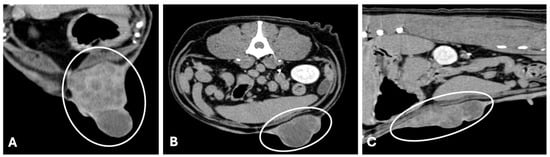

3.2. Computed Tomography